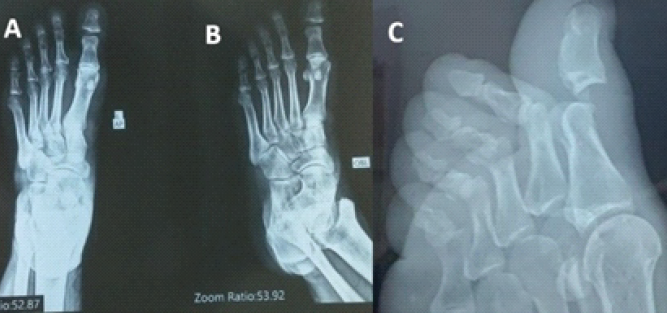

Mechanisms of injury included sports-related trauma, accidental falls, and workplace injuries. Four patients sustained acute injuries, while one presented 3 weeks after trauma with a neglected dislocation. All patients had visible deformity, swelling, and pain of the affected hallux. Standard radiographs confirmed dorsal type II dislocations in four cases and a plantar dislocation in one. True-lateral views were critical in detecting sesamoid incarceration in the delayed case. In all cases, closed reduction failed because the interposed sesamoid bone acted as a mechanical block, preventing congruent reduction of the IP joint. Open reduction was performed in all patients: through medial, dorsal, or L-shaped approaches, depending on chronicity and soft-tissue involvement. Temporary Kirschner-wire fixation was required in all cases to address capsuloligamentous instability. All procedures were performed by a single person (senior author). We present a case of Miki type II dorsal dislocation of the great toe IP joint with incarcerated sesamoid, demonstrating the stepwise approach and management. All the cases were dealt similarly, as described below. Here is an example of a case with a pre-operative radiograph as shown in Fig. 1.

Figure 1: This is a preoperative image of an interphalangeal joint dislocation of the great toe with an incarcerated sesamoid, as shown in anteroposterior, oblique, and lateral images of the left foot (a, b, c).